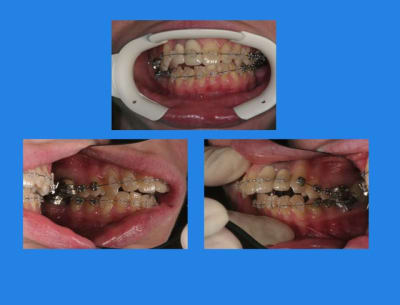

Début du cas :

pose mat Sup.

4mois après, comme ça n’avance pas vite, pose Q.H

et pose du mat. Inf.

contrôle 3 semaines après